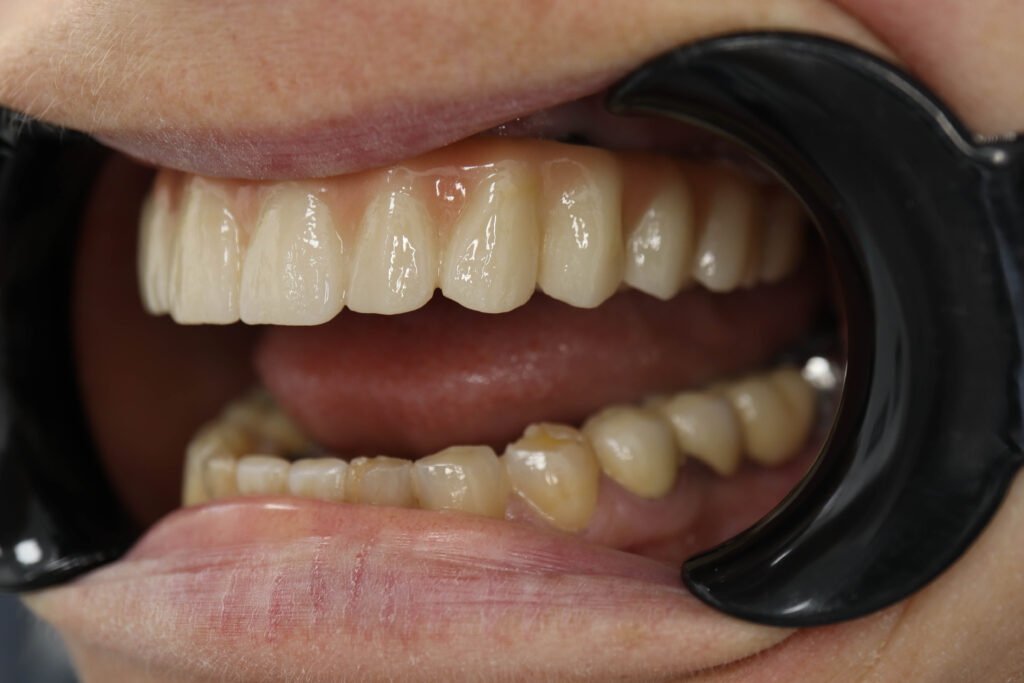

Спустя 25 дней был зафиксирован протез с опопрой на дентальные имплантаты из диоксида циркония.

Результаты